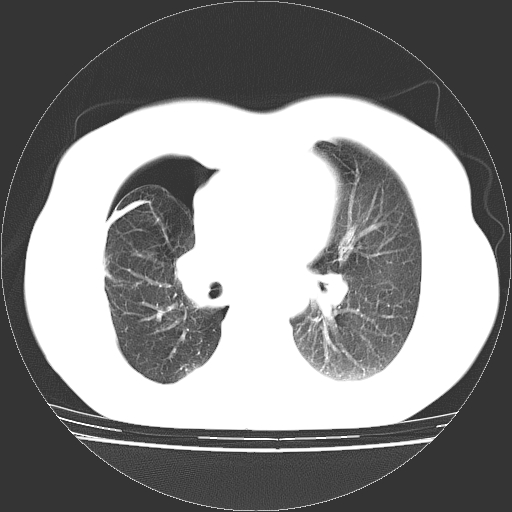

以下是引用zhangzhongshou在2008-3-22 12:52:00的发言:[br]1、右侧液气胸。[br]2、腹水。建议进一步检查。

以下是引用鲁巨ct在2008-3-22 14:10:00的发言:[br]1、右侧液气胸,右中下叶节段性不张。[br]2、腹水,建议上腹部ct检查

以下是引用zjzjr在2008-3-22 17:19:00的发言:[br]1、右侧液气胸,右下叶节段性不张。[br]2、腹水,建议上腹部ct检查